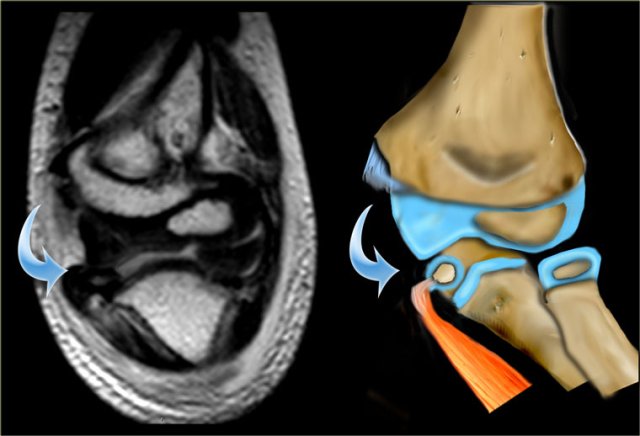

Since most of the structures involved are cartilageneous, it is very difficult to know the exact extent of the fracture.

Sometimes the fracture runs through the ossified part of the capitellum. In those cases it is easy.

The case on the left shows a lateral condyle fracture extending through the ossified part of the capitellum.

This is a Milch I fracture. The elbow is stable.

There is too much displacement so osteosynthesis has to be performed.

MRI can be helpfull in depicting the full extent of the cartilaginous component of the fracture.

The case on the left shows a fracture extending into the unossified trochlear ridge.

The fracture through the trochlear cartilage is so far medial that the ulna is only supported on the medial side.

This means that the elbowjoint is unstable.

Continue with the MRI.

The MR shows the small medial epicondyle with tendon attachement trapped within the joint.

The avulsed medial epicondyl was found within the joint and repositioned and fixated with K-wires.